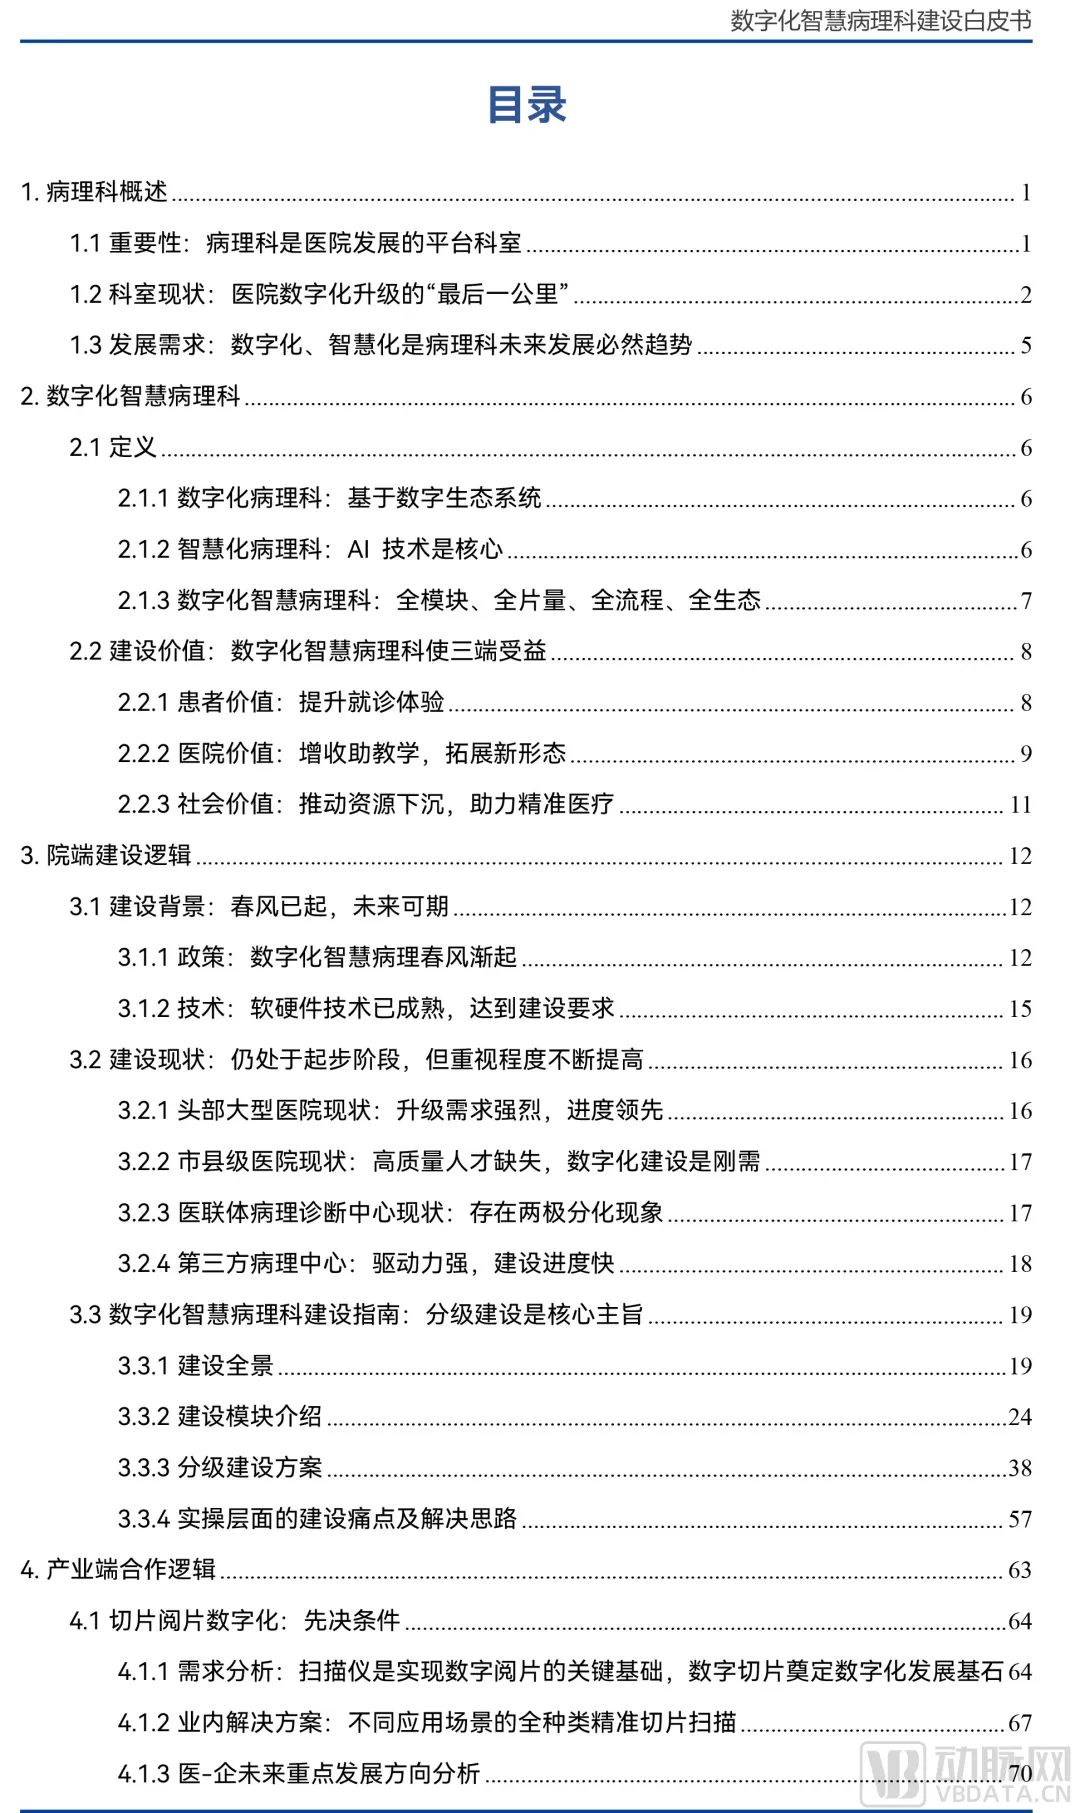

以下为报告全文目录: